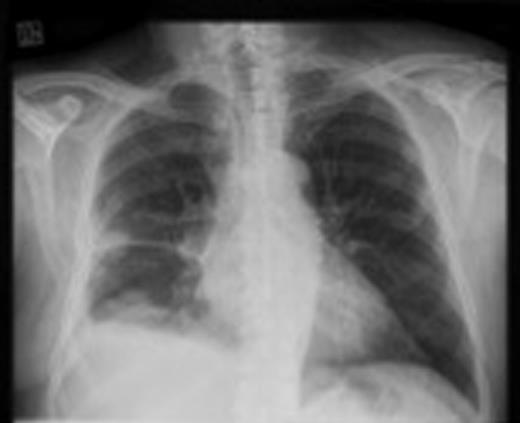

We report a case of a 62-year-old gentleman who presented with shortness of breath and right-sided chest pain over the period of 12 months. A chest X-ray showed a right pleural plaque that subsequently caused a right pleural effusion (Fig. 1). Decortication, pleurodesis and pleural biopsy were performed with histopathology confirmation of mesothelioma. He declined chemotherapy or radiotherapy, although he was having regular follow-up by the oncologist.